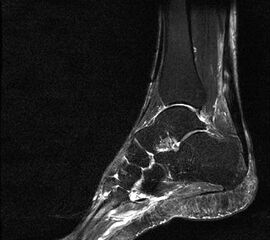

In Abhängigkeit des gesamten klinischen Bildes und der Vorgeschichte kann ein MRT z.B. zum Ausschluss einer Stressfraktur oder Ruptur der Plantarfaszie erforderlich werden. Es hat sich bewährt, in Fällen eines mehrmonatigen Krankheitsverlaufes und sonographisch verdickter Plantarfaszie >8mm (Normwert <4mm) vor Therapiebeginn ein MRT zum Ausschluss von Teilrupturen durchzuführen. Obwohl auch in diesen Fällen eine Stoßwellentherapie erfolgen kann, ist eine derartige Information aus juristischen Gründen von Bedeutung.

Hier befindet sich ca. 3-5 cm proximal des Tuber calcanei ein als „kritische Zone“ benannter Bezirk, der durch eine ungünstige arterielle Blutzufuhr gekennzeichnet ist (letzte Wiese). Hier finden sich häufig spindelförmige Schwellungen, die bei MRT-Diagnostik nicht selten partielle Nekrosen und Partialrupturen der Achillessehne aufweisen (Abb. 14).

Die sonographische Diagnostik eignet sich primär zur Erkennung schmerzhafter Prozesse im Verlauf der Achillessehne und kann bei Bedarf durch Röntgen bzw. MRT ergänzt werden. Besonders bei längeren Verläufen und kräftigen spindelförmigen Schwellungen (>9mm, Normwert <5mm) im Bereich der kritischen Zone sollte ein MRT zum Ausschluss von Nekrosezonen und Partialrupturen vor Therapiebeginn veranlasst werden. Die sonographisch leicht zu erfassende Veränderung der Sehnendicke im mittleren Sehnenanteil ist ein guter Indikator für die Schwere der Erkrankung und die Beurteilung des Behandlungsverlaufes. Die sichtbaren Veränderungen am distalen knöchernen Ansatz der Sehne sind diskreter.